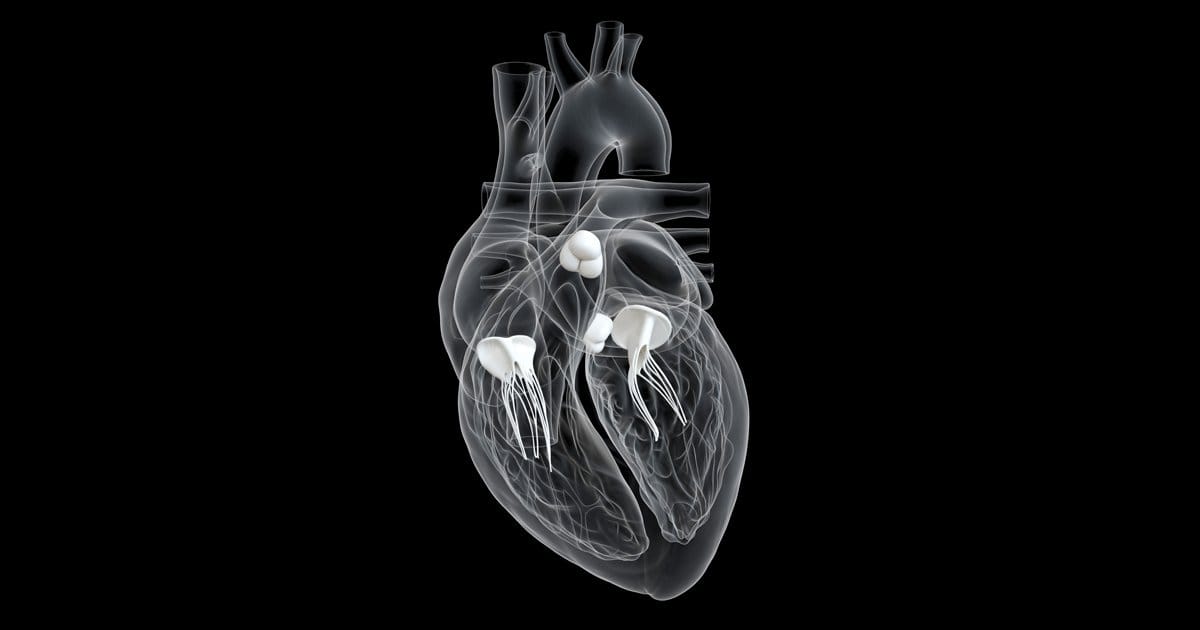

At ICE Prospective Healthcare, your cardiopulmonary health and physical well-being are our top priorities. We are committed to supporting you through every step of your journey with ICE—whether you are an online member or a client of our in-person personal training services. From providing weekly personalized care plans and assessments to consulting with you on your unique concerns and goals, we are here to guide and empower you. All of our services are delivered through personalized consultations and scheduled appointments, ensuring the highest quality of care for each and every client.

CARDIOPULMONARY EXERCISE TRAINING- implementing exercises that boost cardiac and pulmonary functioning known as ICE, to prevent and manage cardiac and pulmonary complications.

"Our mission is to emphasize educating the public by introducing interventional methods of cardiac & pulmonic preventative cares through exercise science and assessments"

take control of your heart and lungs with ICE.